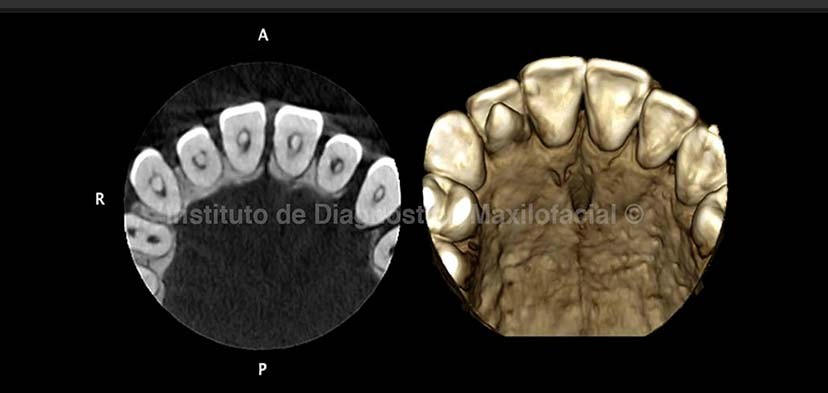

A la tomografía volumétrica confirmamos la presencia de una alteración en la morfología coronaria caracterizada por la presencia de una cúspide supernumeraria en la cara palatina de la pieza 1.2 sugerente de cúspide en talón, además de cálculos pulpares. (Fig. 2)